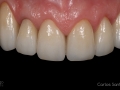

As Facetas Cerâmicas (lentes de contacto dentárias ou laminados), permitem corrigir da maneira mais estética e conservadora possível, problemas de forma e tamanho, côr e posição dos dentes, bem como substituir restaurações antigas e inestéticas.

São aderidas químicamente ao esmalte dentário de uma forma permanente, com o objectivo de melhorar a estética dos nossos pacientes.